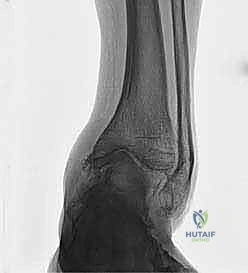

1. الكسور الملتئمة بشكل خاطئ (Malunion of Fractures)

يُعد هذا من أكثر الأسباب شيوعاً في مجتمعاتنا. عندما يتعرض الشخص لكسر في عظم الظنبوب أو الشظية بالقرب من مفصل الكاحل، ولا يتم تجبيره أو تثبيته جراحياً بالزوايا التشريحية الصحيحة، يلتئم العظم في وضع معوج.

مثال سريري واقعي: مريض تعرض لكسر في الظنبوب والشظية قبل 26 عاماً، وتم علاجه بشكل تحفظي (بالجبس) دون تصحيح كامل للزاوية. بعد مرور ربع قرن، تطور لديه تشوه فحجي (تقوس للداخل) مع آلام شديدة نتيجة تآكل الغضروف الداخلي. في مثل هذه الحالات، قطع العظم هو الحل الجذري.